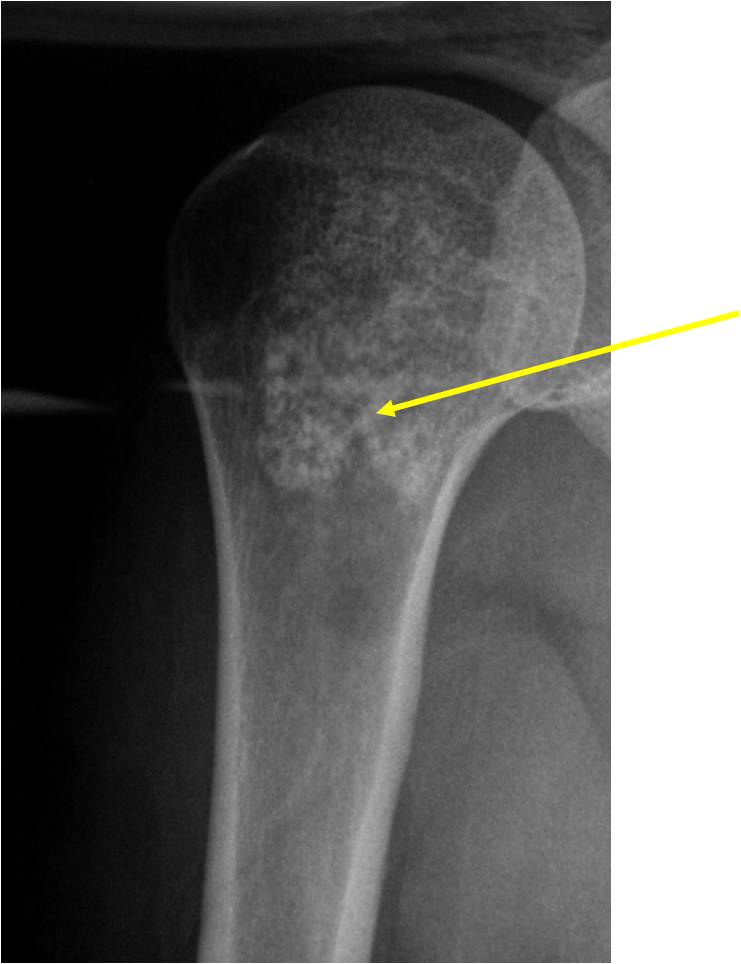

- Localized, radiolucent defect usually with punctate calcifications

- Calcifications are typical but not always present

- Matrix may demonstrate various degrees of calcification

- Calcifications are stippled, punctate, popcorn like calcifications and “Ring and Arc” calcifications

- Cartilage tumors grow in a lobular manner. The perimeters of the lobules undergo

- enchondral ossification that may calcify. If the entire perimeter of the lobule calcifies it appears

- radiographically as a “Ring”. If a portion of the perimeter of a lobule calcifies it forms an “Arc” on

- an X-ray.

Plain X-Ray:

- Geographic lytic lesion

- Central often metaphyseal in long bones

- Can be eccentric also

- Expansile remodeling with thinned cortex

- Chondroid matrix with calcifications in majority of tumors

- Approximately 20% have limited or no calcifications